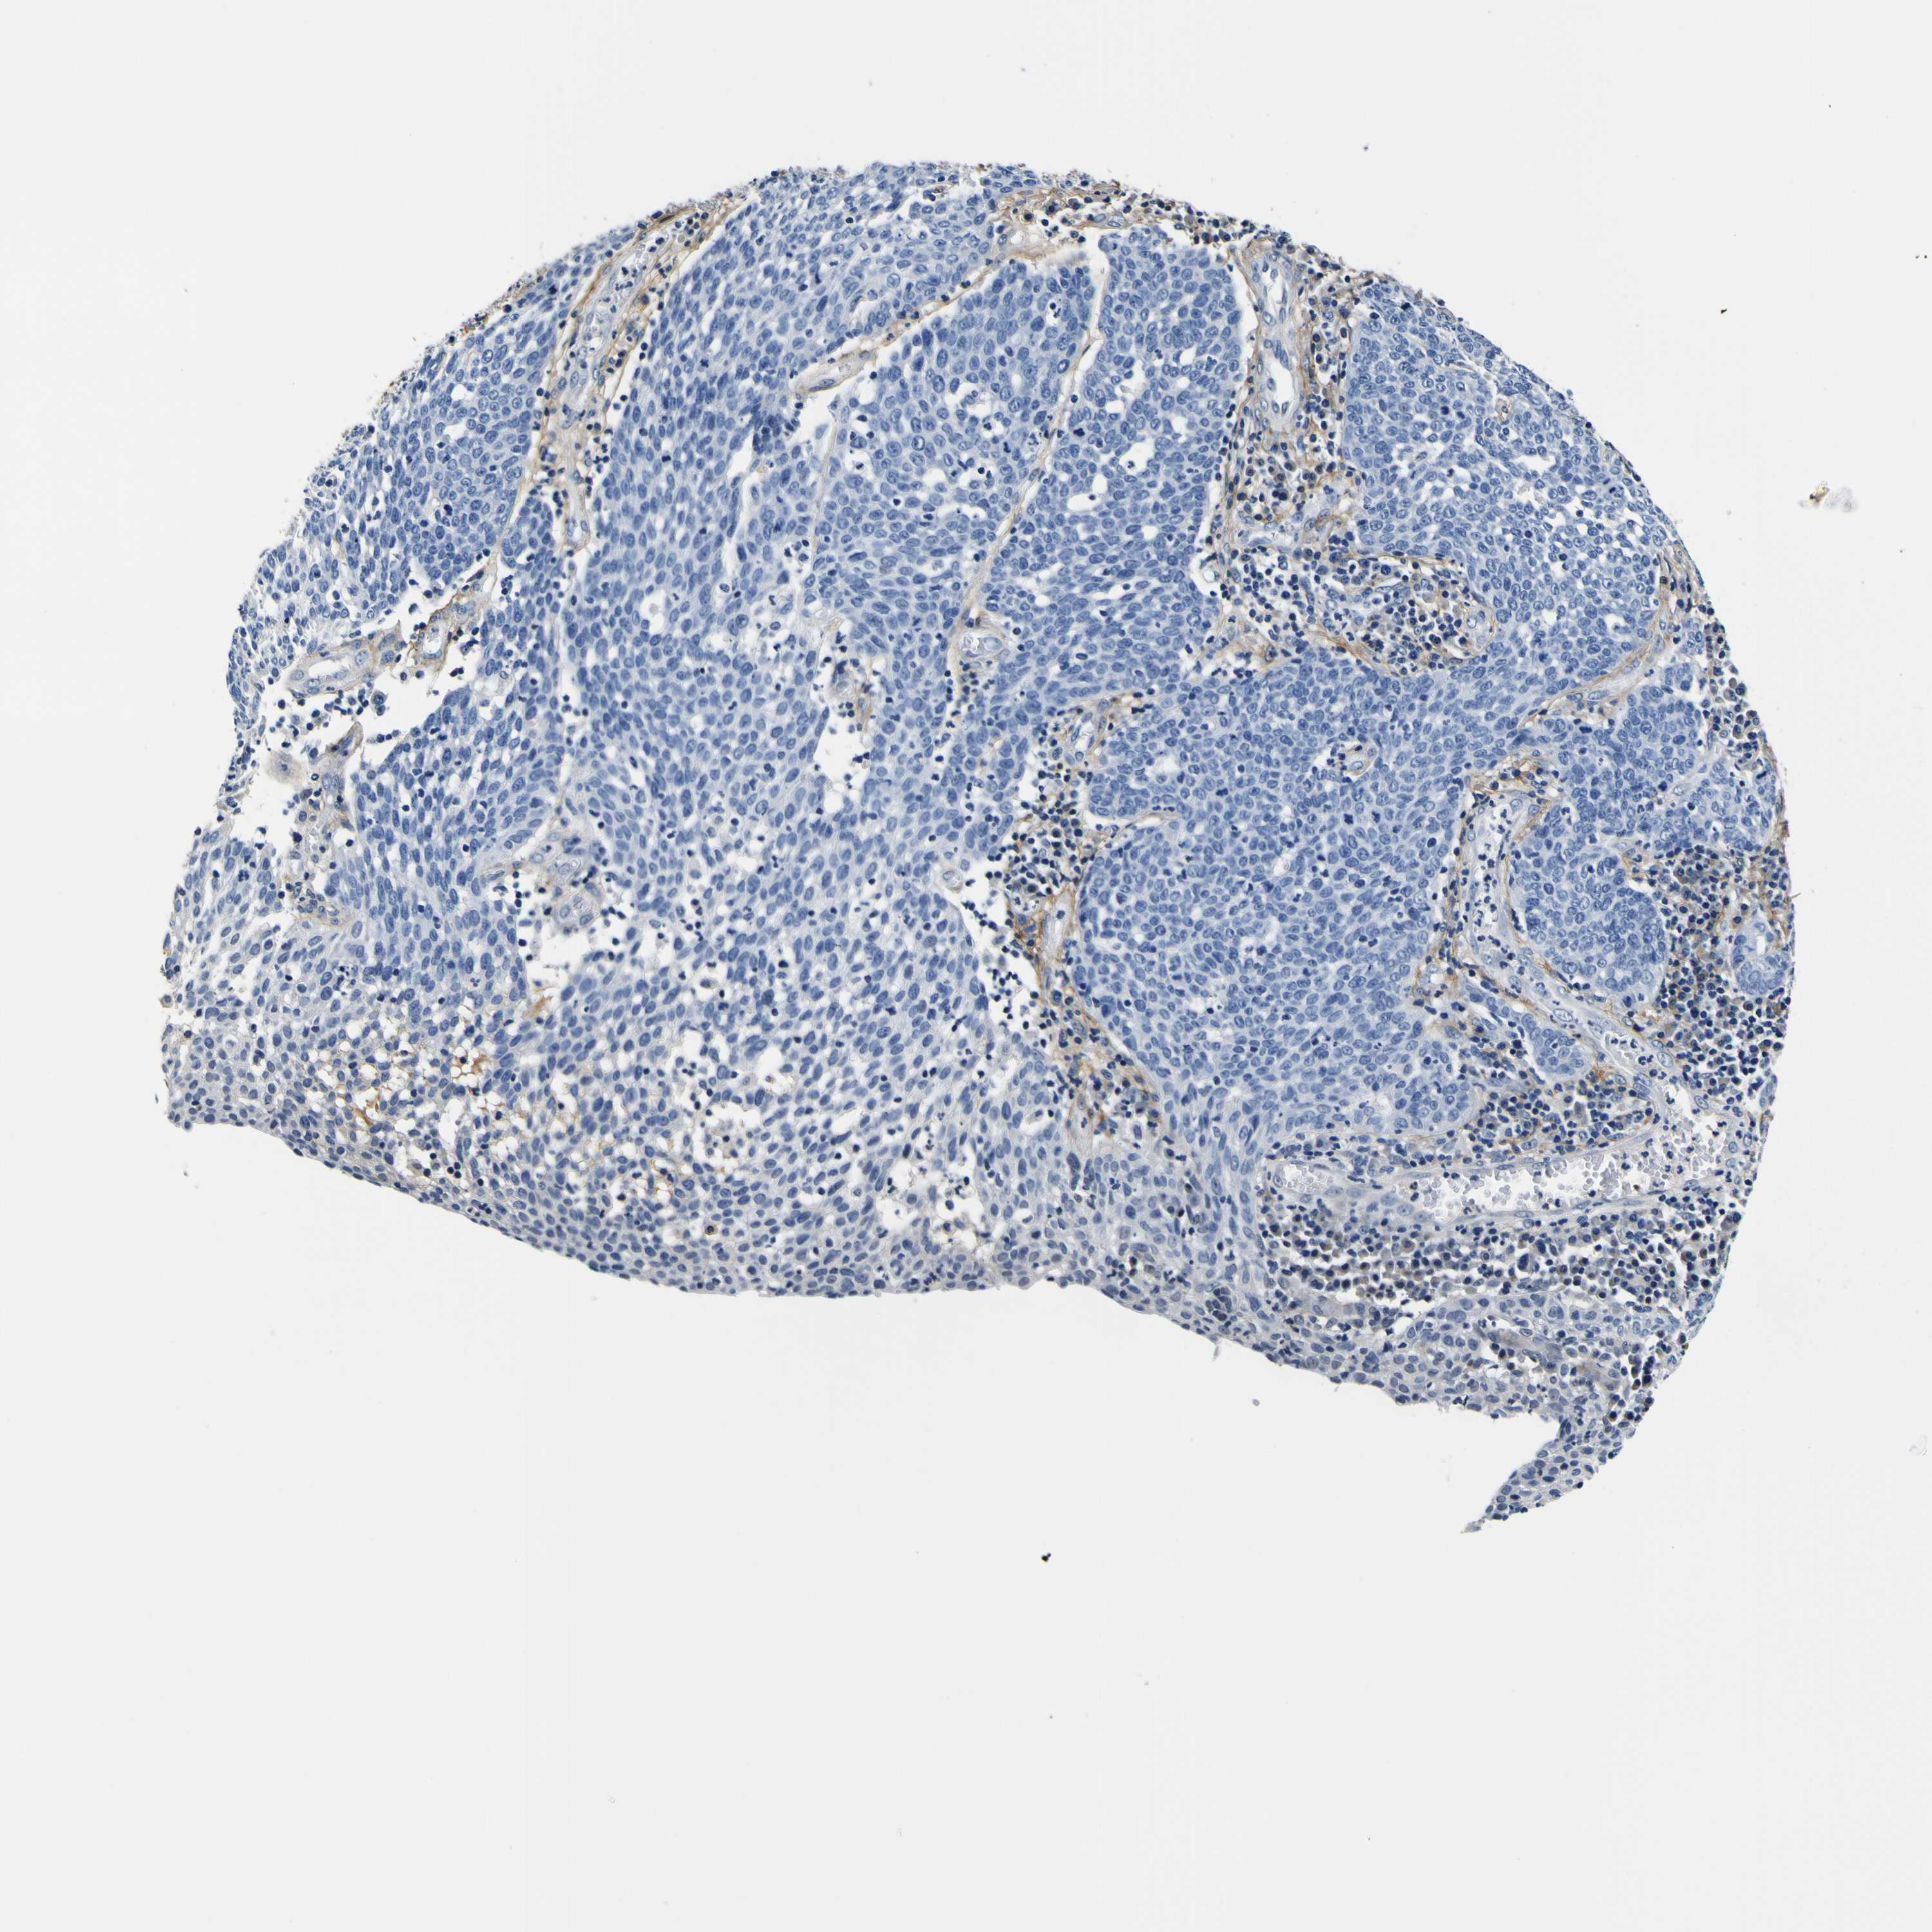

CERVICAL CANCER - Protein expressioni

A mouse-over function shows sample information and annotation data. Click on an image to view it in a full screen mode. Samples can be filtered based on level of antibody staining by selecting one or several of the following categories: high, medium, low and not detected. The assay and annotation is described here.

Note that samples used for immunohistochemistry by the Human Protein Atlas do not correspond to samples in the TCGA dataset.

Antibody stainingi

Antibody staining in the annotated cell types in the current human tissue is reported as not detected, low, medium, or high, based on conventional immunohistochemistry profiling in selected tissues. This score is based on the combination of the staining intensity and fraction of stained cells.

Each image is clickable and will lead to virtual microscopy that enables deeper exploration of all samples and also displays staining intensity scores, fraction scores and subcellular localization as well as patient and tissue information for each sample.

Antibody HPA012306

Staining

High

Medium

Low

Not detected

Intensity

Strong

Moderate

Weak

Negative

Quantity

>75%

75%-25%

<25%

None

Location

Nuclear

Cytoplasmic/membranous

Cytoplasmic/membranous,nuclear

Squamous cell carcinoma, NOS

Adenocarcinoma, NOS